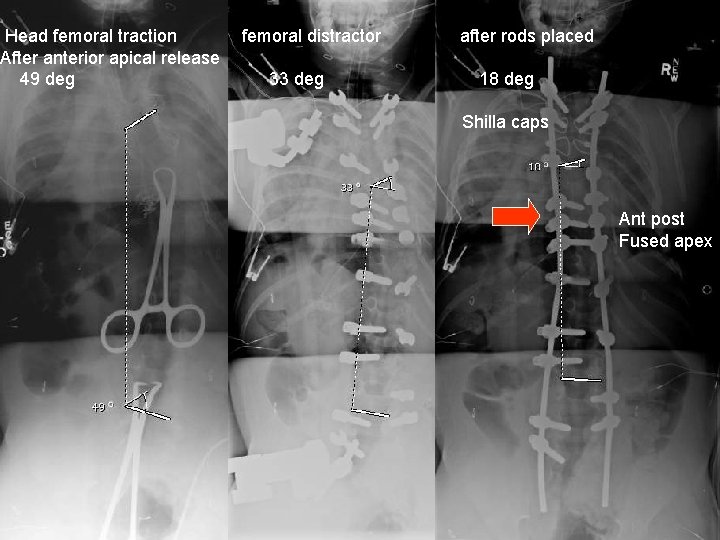

Head femoral traction After anterior apical release 49 deg femoral distractor 33 deg after rods placed 18 deg Shilla caps Ant post Fused apex